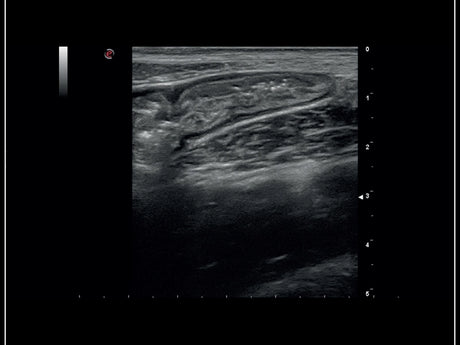

La qualité d’image est au cœur de la philosophie Esaote. Grâce à ses sondes de dernière génération et à son traitement du signal avancé, la marque permet une visualisation fine des structures anatomiques, même les plus profondes. Leurs échographes intègrent des écrans tactiles haute résolution, une interface claire et une connectivité complète, favorisant un flux de travail rapide et efficace.

Les échographes Esaote offrent une restitution d’image d’une grande précision, permettant un diagnostic fiable dans toutes les spécialités. Le traitement numérique optimise le contraste et la netteté, réduisant les artefacts et améliorant la détection des tissus pathologiques. Ces performances sont particulièrement appréciées en gynécologie, où la lisibilité des structures pelviennes ou obstétricales est déterminante.